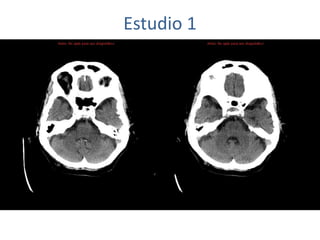

Estudio 1